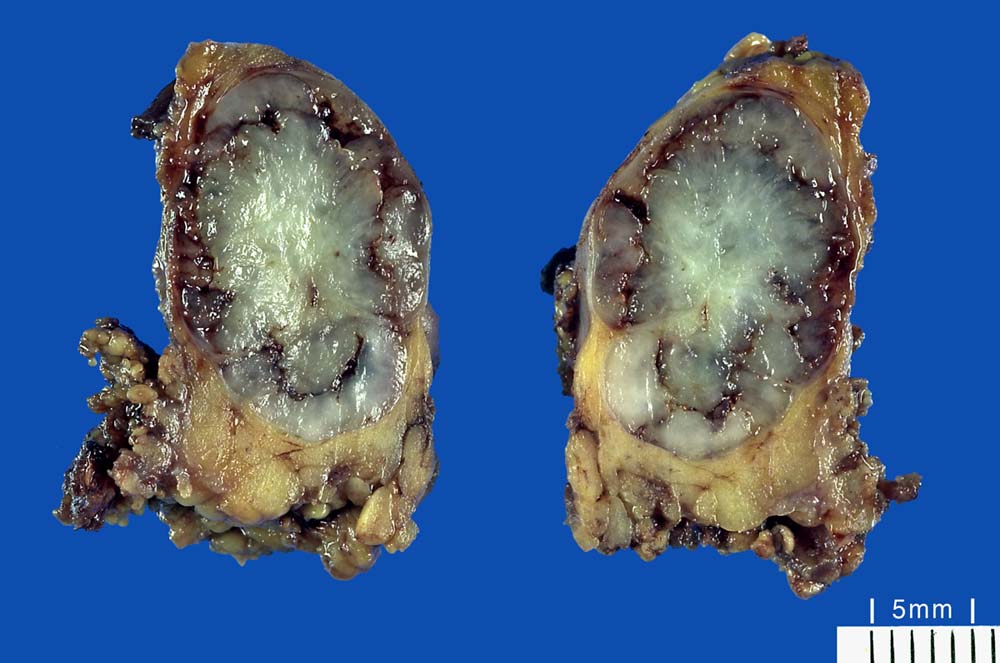

Pleomorphes Adenom der Speicheldrüse

Grauweisser glasiger Knoten im lobulierten ockerfarbenen Speicheldrüsenparenchym.

Parotistumor

Makroskopie